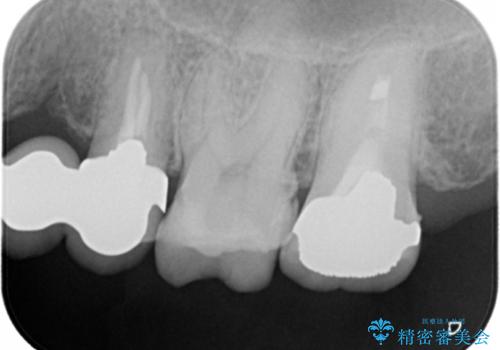

- 左上の奥歯がたまにしみるとのことで来院。視診・レントゲン画像より明らかに劣化した不適な修復物を確認しました。

同じ材料で同じように修復し直してもまた同じような予後になることが予想されるため、適合の良いセラミックインレーでの治療を提案させていただきました。

しかし向かい合わせになる歯の咬みこみが強く、インレーでは破折してしまうリスクが高いと予想し、より強固なクラウンで修復することになりました。